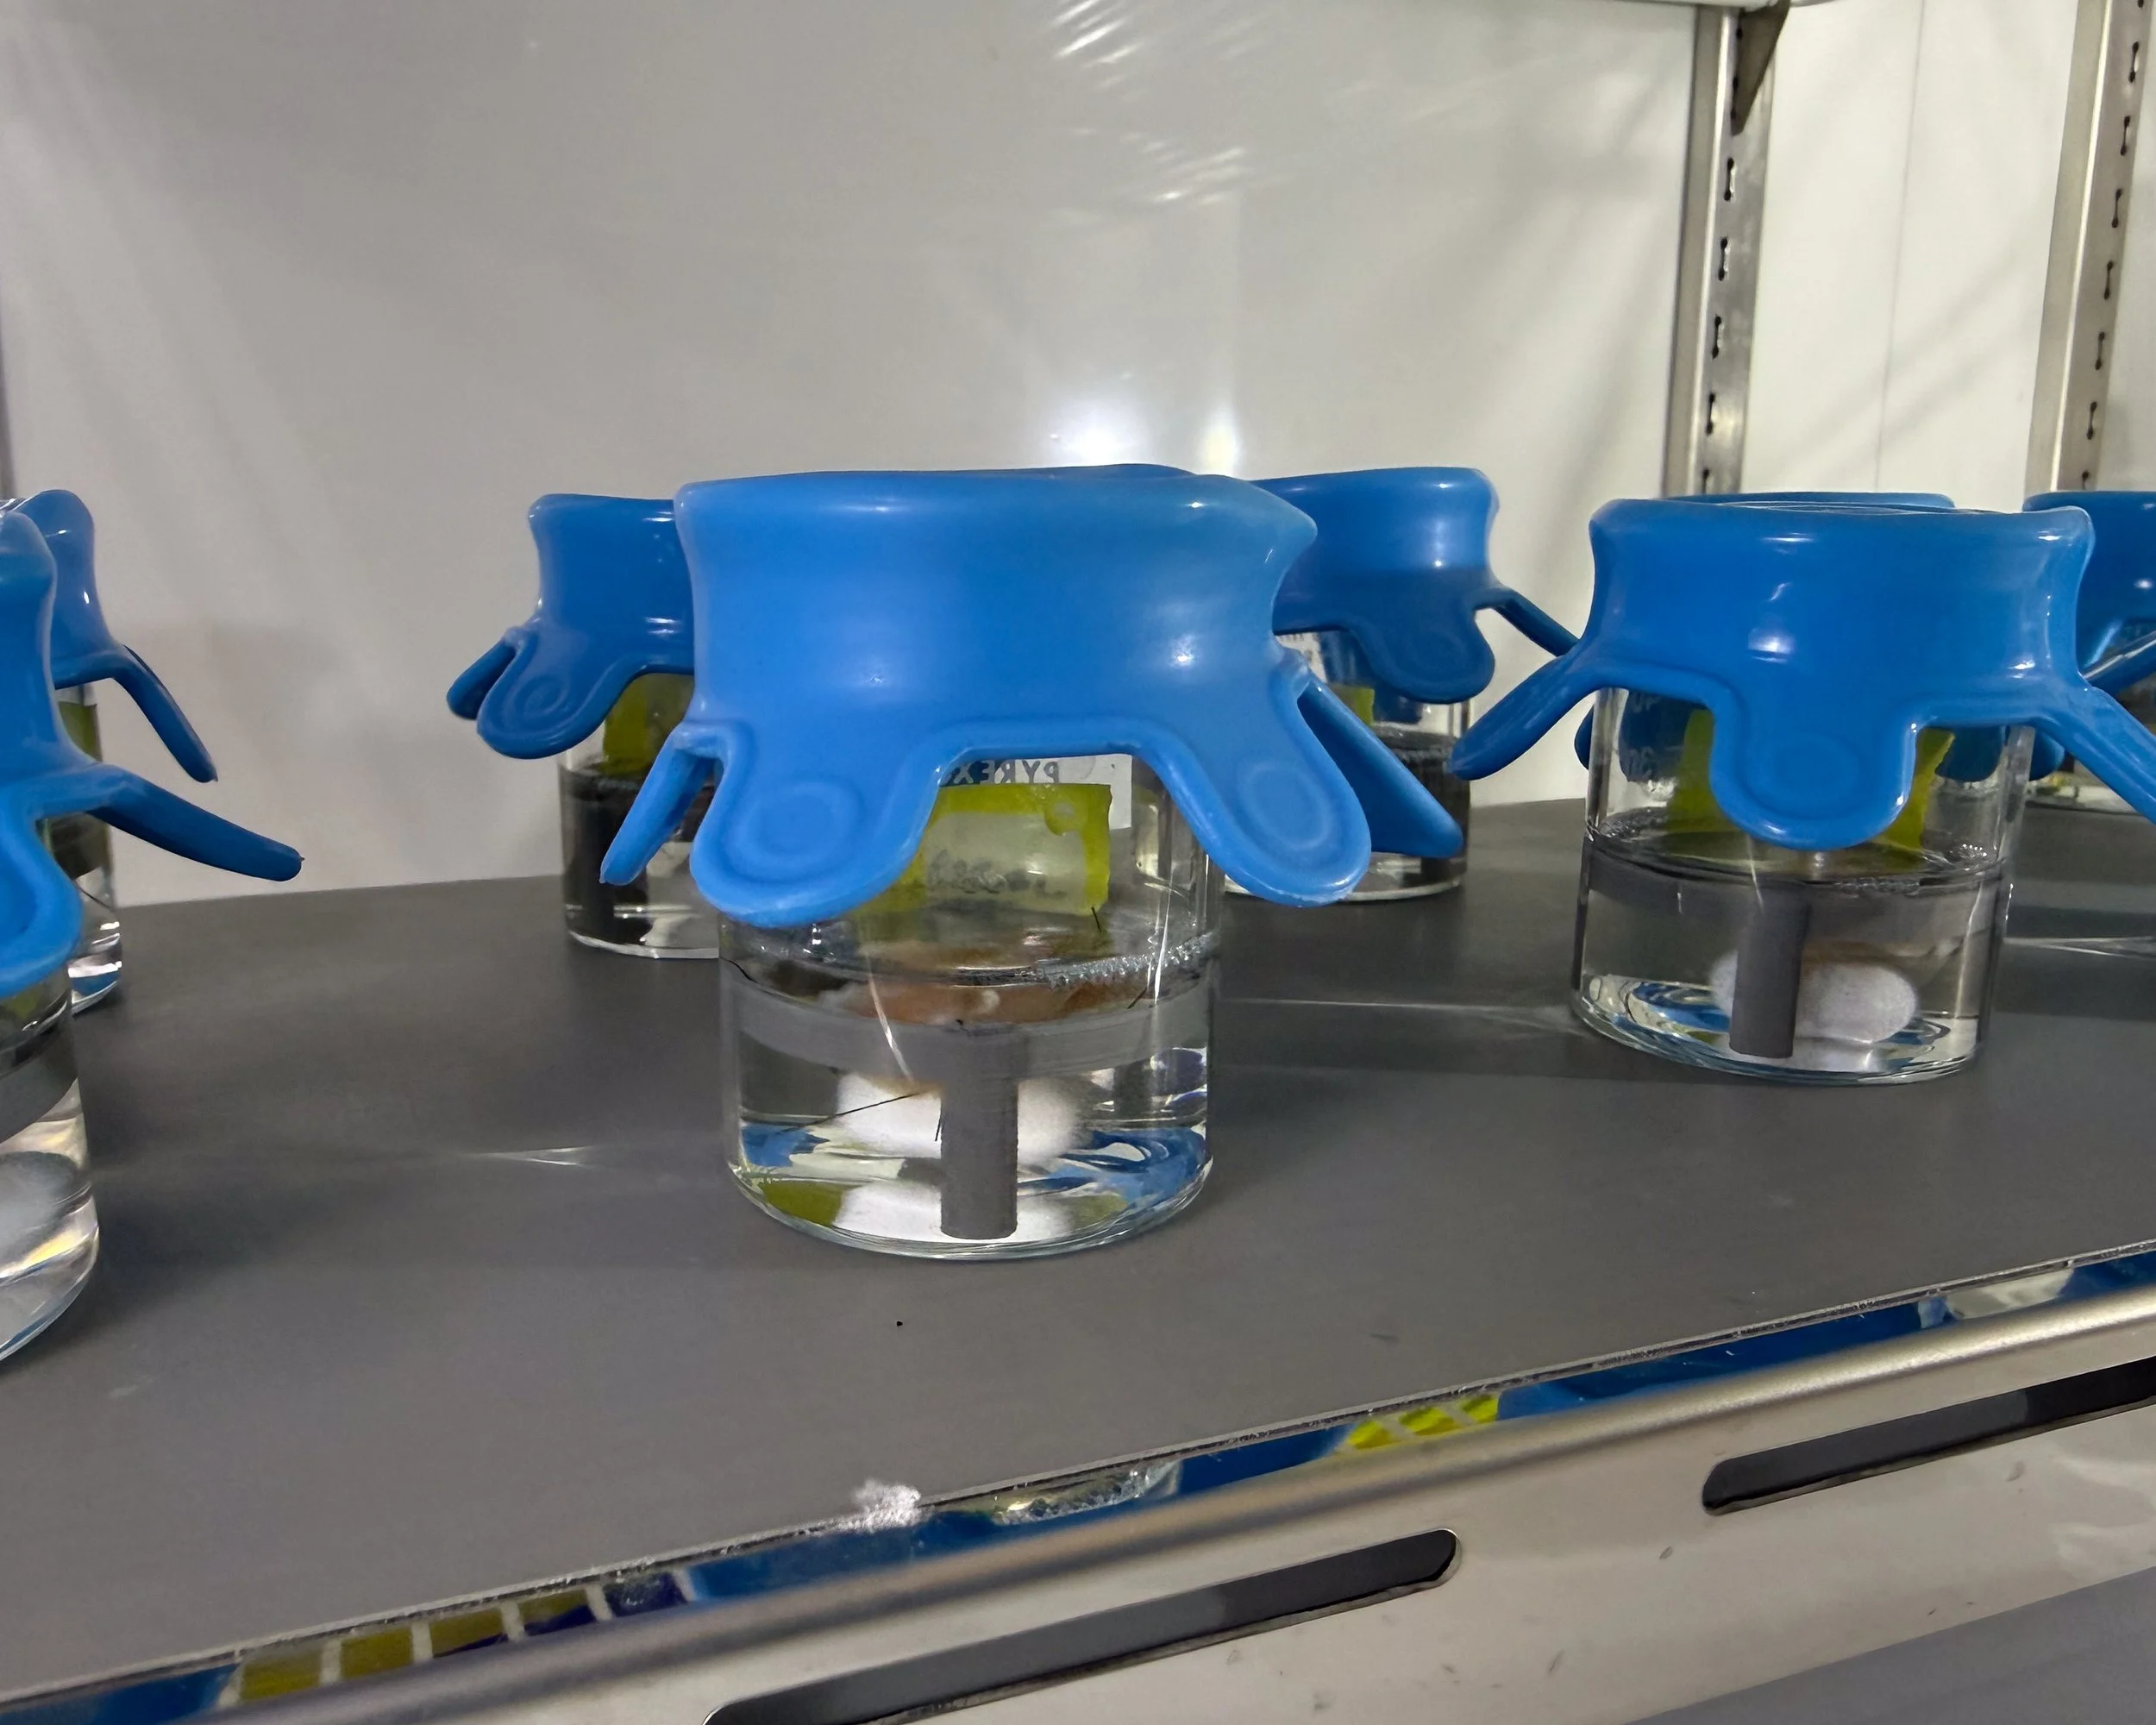

Gallery: DMM in development at the Sarcogenics lab

Remove cells, keep structure

Donor muscle tissue is processed to strip away all living cells, leaving behind the extracellular matrix — a natural scaffold made of proteins like collagen, laminin, and fibronectin.